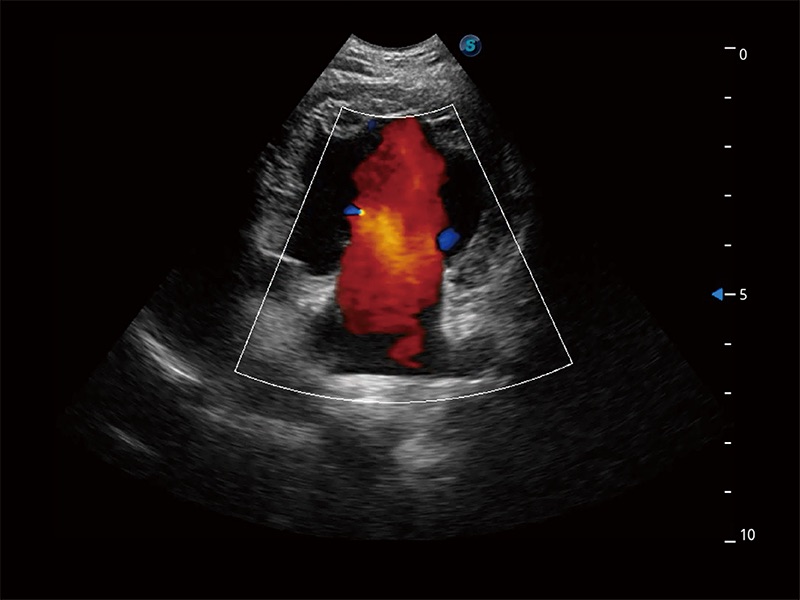

在传统二维血流成像的基础上,呈现血流的立体感,具有动感的生命力之美。即便是微小的血管也能轻松应对,提高了血流的视觉敏感性。

ProPet 80 配备了丰富的心脏探头群、先进的成像技术和专业的心脏测量工具,可帮助动物医生为不同体型和生理结构的动物提供心脏和心肌功能的全面评估。

实时用颜色表示心肌组织运动,观察和定量组织的运动情況,对快速检测与评估心肌的灌注和活性、电传导及心肌收缩和舒张功能等均能提供重要的诊断信息。

ProPet 80 全新的动物超声智能软件和丰富的探头群,为动物医生提供了高清晰度和精细分辨率的图像,无论在宠物、马科、畜牧还是实验室动物等应用中都可以轻松应对,为您的日常工作带来满意的体验。